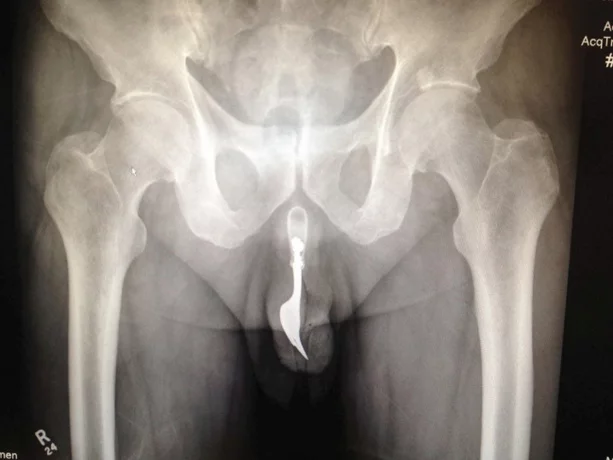

Ну у вас и вечерние беседы вышли...Надеюсь никто себе ничего в печальные места не запихивал?:D